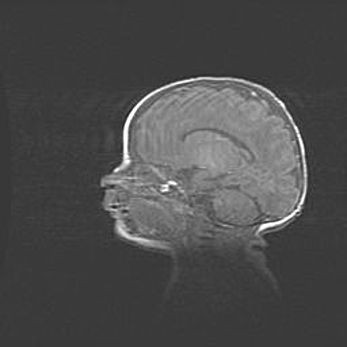

Аномалия Денди-Уокера. Признаки гипоплазии мозолистого тела.

Возраст: 5 месяцев 3 дня

Вес: 5550 г

Пол: мужской

Окружность головы: 39 см

Срок гестации: 40 недель

Аномалия Денди-Уокера – это порок развития головного мозга, для которого характерна триада симптомов: гипотрофия или аплазия червя мозжечка и/или полушарий мозжечка, расширение четвёртого желудочка с формированием ликворной кисты задней черепной ямки, гипертензионная гидроцефалия различной степени.

Гипоплазия мозолистого тела относится к дефектам внутриутробного этапа развития мозговой ткани, возникающим в процессе закладки структур головного мозга, что происходит на начальных этапах развития эмбриона.